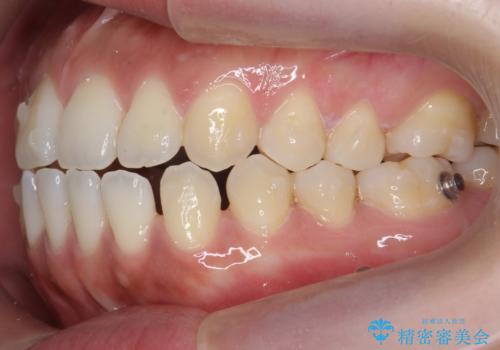

受け口、すきっ歯を インビザラインで モニター治療

- 前歯のすき間と受け口を気にして来院。

マウスピースでしっかり閉じています。

下の前歯を後方に移動するため、ゴムを上下のマウスピースにかけてもらいました。